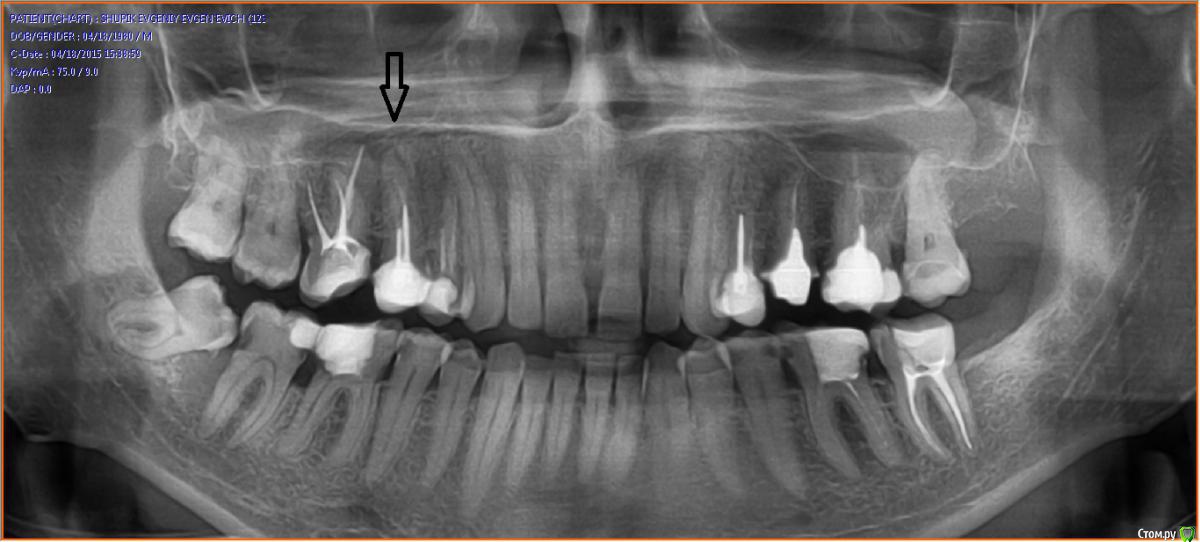

garett Опубликовано 29 сентября, 2015 Автор Поделиться Опубликовано 29 сентября, 2015 Прикладывайте какой есть. но думаю необходимо будет сделать свежий.Стрелкой отметил этот зуб. Там виден большой карман и, как я понимаю, в него проникла инфекция. Сегодня болит меньше (временами вообще не беспокоит), но припухлость локализовалась аккурат между 5 и 6 зубами. Жевать не больно ни на 5, ни на 6 зубы. Постукивание по ним тоже не вызывает дискомфорта. Но вот если надавить на эту шишку - пронзает просто. И боль именно острая, как при порезе. Зубы так не болят, там боль ноющая. Еще неделю назад все было в норме. Ссылка на комментарий

St. Опубликовано 29 сентября, 2015 Поделиться Опубликовано 29 сентября, 2015 По этому снимку в 5 зубе неидеально запломбированы каналы и видно небольшой воспалительный процесс на верхушке корня. Это может вызывать описанный Вами дискомфорт. Помимо этого есть определенные проблемы в других зубах. Ссылка на комментарий

garett Опубликовано 1 октября, 2015 Автор Поделиться Опубликовано 1 октября, 2015 (изменено) Выздоравливайте Отек 2-3 суток на месте разреза - это нормально, потом должен уменьшаться постепенно. Антибиотики пейте, причем обязательно назначенное количество дней, не бросайте раньше даже если полегчает.Если интересно - сегодня был у терапевта, начали было распломбировывать проблемный 5-й зуб и не удалось извлечь один из штифтов. Вкручен намертво, причем довольно глубоко. Очень не хочется удалять этот зуб, он крепко сидит, каналы вроде бы хорошие, неужели из-за того, что штифт не получилось пока убрать, я должен лишаться зуба? Ну вот на снимке видно, наверное - там один штифт чрезвычайно длинный. Что Вы думаете по этому поводу?P.S. Аргументируют так, что если даже высверлить этот штифт, потом стенка будет тонкая и вкладку не получится поставить. Для примера - такой же точно 5 зуб справа - тоже было 2 штифта, их убрали и поставили вкладку (коронка на момент создания снимка еще не была готова). И отлично все. Может быть, имеет смысл в другую клинику сходить? Это дело такое, зуб потом не вернешь. Изменено 1 октября, 2015 пользователем garett Ссылка на комментарий